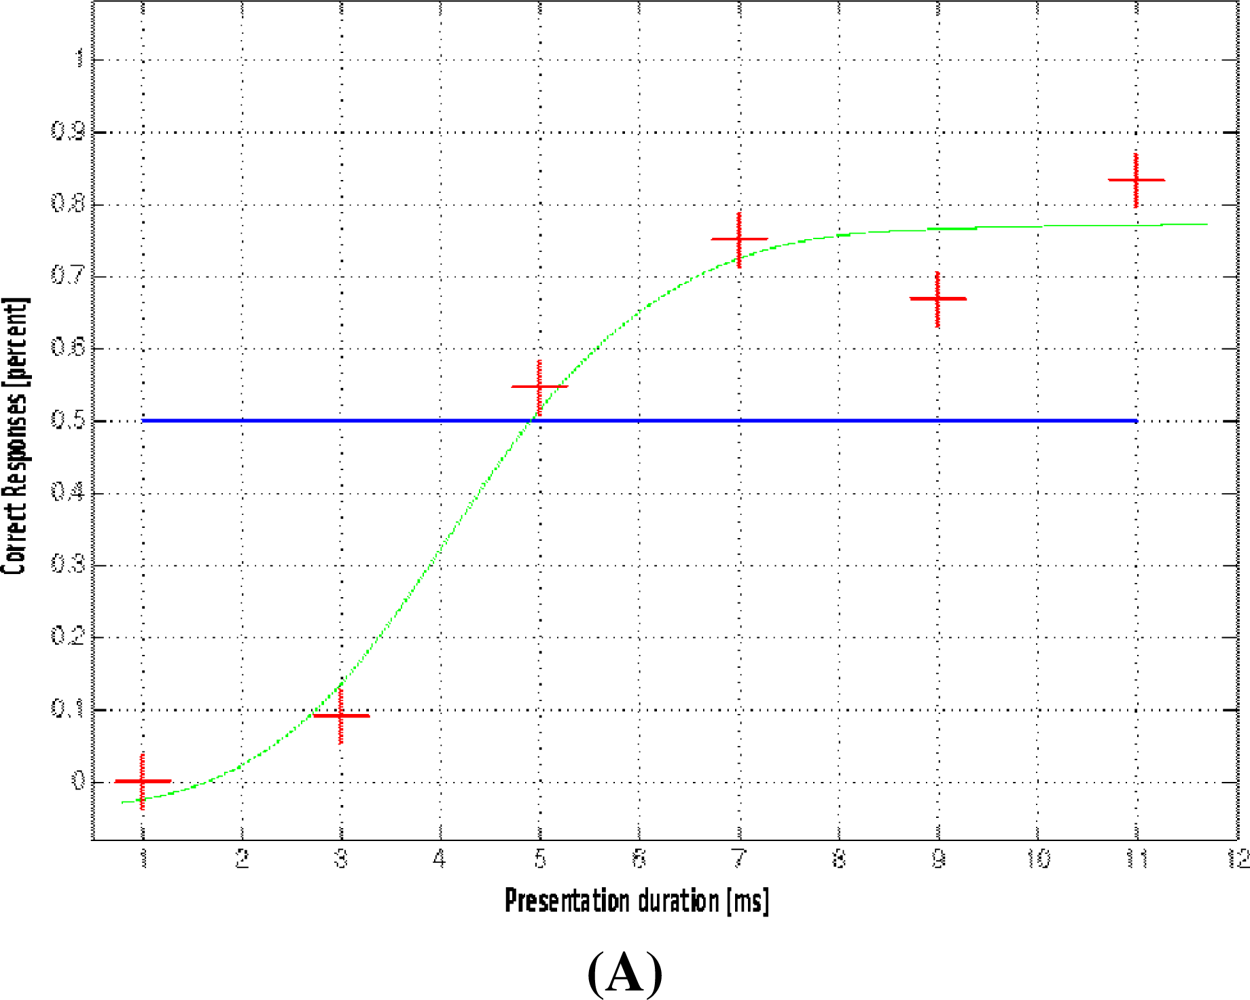

2.2. Functional MRI

2.3. Multi-Modal Integration of MRI, fMRI, and Slow Cortical Potentials (SCP, DC-EEG)

Functional brain imaging: